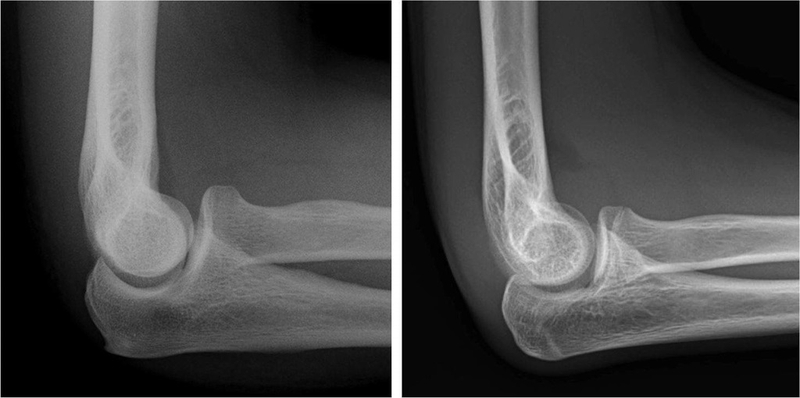

Sự chèn ép hoặc co kéo của dây thần kinh trụ xảy ra tại khuỷu tay được gọi là hội chứng đường hầm xương trụ hay hội chứng đường hầm khuỷu tay. Tùy thuộc vào vị trí dây thần kinh trụ bị chèn ép mà bệnh nhân sẽ có biểu hiện đau, tê vùng khuỷu tay, bàn - ngón tay, cổ tay. Thần kinh trụ đôi khi bị chèn ép tại vùng cổ hoặc cổ tay nhưng phổ biến nhất là ở phía sau khuỷu tay.

Bác sĩ sẽ dựa vào việc thăm khám khuỷu tay và bàn tay cùng các triệu chứng lâm sàng để xác định, chẩn đoán xem dây thần kinh trụ có bị chèn ép hay không, từ đó xác định vị trí bị chèn ép.

Các biện pháp chẩn đoán cận lâm sàng để thăm khám hội chứng đường hầm xương trụ có thể kể đến là: